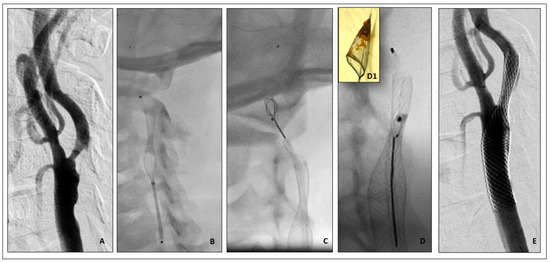

- (5)

- Vascular access site complications

- Brief Complication description: